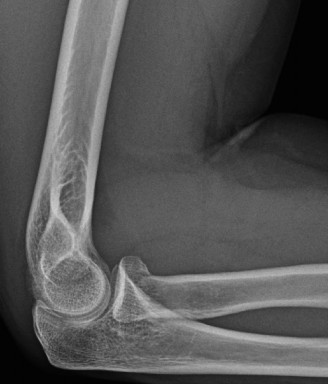

Imaging should include x-rays, which may demonstrate posterior glenoid bone loss or an impaction fracture on the anterior-superior humeral head (Fig. 2–38). CT images with 3D reconstructions can be very useful when assessing the extent of glenoid bone loss and evaluating glenoid and humeral version. Normal glenoid version is from −2 to −8 degrees of retroversion, and this may be increased in posterior instability. MRI can also be useful when assessing the posterior labrum (Fig. 2–39).

Figure 2–38 Radiographs showing a posterior shoulder dislocation.